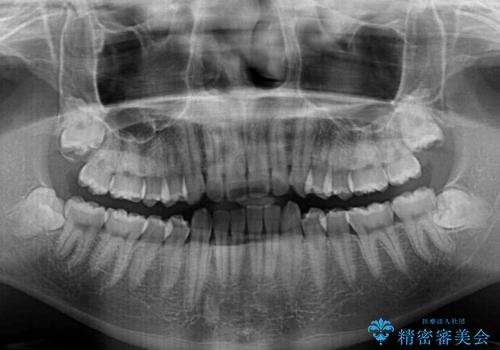

- 前方に傾斜した前歯を気にして来院された患者様です。

強く食いしばってしまう癖があり、下顎前歯に押し出されて上顎前歯が前方へ斜めに突き出している状態でした。

IPR(歯と歯の間を削る)を多用して、インビザラインにて矯正治療を行うこととしました。